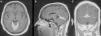

Enfermedad de Erdheim-Chester con afectación meníngea: presentación de un caso clínico

Erdheim-Chester disease with meningeal involvement: A case report